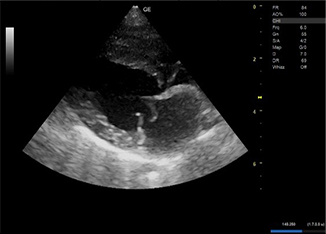

明らかな腹水貯留は認められなかった。 - 心エコー図検査にて、僧帽弁の逸脱とそれに伴う僧帽弁逆流が認められた。

- 以上から心原性肺水腫と診断した。